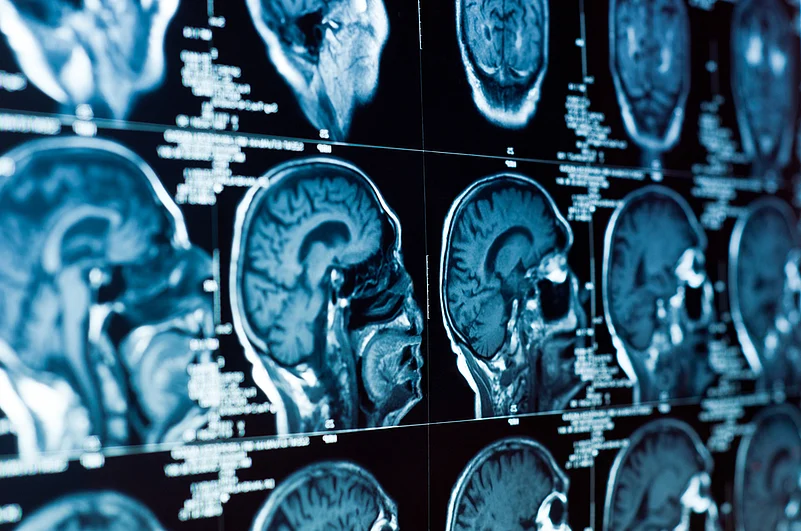

A brain tumour is a collection or mass, of abnormal cells in the brain. The skull, which encloses the brain, is very rigid. Any growth inside such a restricted space can cause problems. Brain tumours can be cancerous (malignant) or noncancerous (benign). When benign or malignant tumors grow, they can cause the pressure inside the skull to increase. This can cause brain damage, and it can be life-threatening.